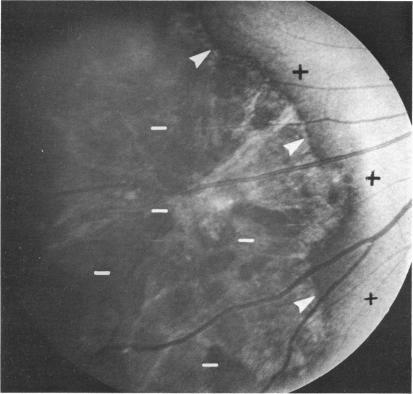

The following is a brief summary of the results in our ten groups of cases. The positive features of laser scotometry are emphasized. The normal response is well defined: there are no uncertain blind spot margins. The peripheral field is probably extended beyond 60 degrees nasally and superiorly. The size and shape of the small central scotomas associated with macular holes are easily defined and correlated directly with the visible edge of the hole. This result is distinct from the intact subjective response with cystoid maculopathy and surface wrinkling retinopathy. Plotting the margins of peripheral abnormalities such as retinal detachments, retinoschisis, and lattice degeneration is easily done. Schisis is distinguished by an absolute scotoma. This scotometry is facilitated by a larger "normal" field with the laser instrument. Lattice degeneration causes a field defect. A branch retinal artery occlusion shows a slightly jagged border, difficult to detect by standard methods. A cotton-wool spot does not show a total nerve-fiber-bundle defect. Small absolute scotomas are correlated with degenerative changes within nevi. Degenerative changes over small melanomas--ie, the orange spots--also produce absolute field defects. "Bear track" lesions have a normal field, whereas dense black isolated lesions are associated with absolute scotomas. In macular degeneration the bright laser test object is usually visible to the patient within detachments of neuroepithelium, detachments of the pigment epithelium, and over recent subretinal neovascularization. Response is absent over sharply-defined zones of pigment atrophy and over late subretinal fibrovascular mounds. In contrast to the degenerative cases, a selection of hereditary cases showed no direct correlation between the zone of pigment atrophy and the zone of absolute scotoma. The scotoma was much larger than the atrophic region, extending to the edge of the cream-colored subretinal spots. The laser target method sharply defines the absolute scotoma associated with papilledema. It also detects a slit-like nerve-fiber-bundle defect, suggesting progressive damage. Small, but possibly not the earliest, scotomas associated with glaucoma can be detected with laser scotometry. In some cases they are detected when the Goldmann perimetric field is normal. Late residual visual fields are easily defined, since fixation can be directly monitored. The vertical border of hemianopic defects can be defined within one degree of accuracy.

以下是我们十组病例结果的简要总结。重点强调了激光扫描视野检查的阳性特征。正常反应定义明确:盲点边缘不存在不确定性。周边视野在鼻侧和上方可能扩展超过60度。与黄斑裂孔相关的小中央暗点的大小和形状易于界定,且与裂孔的可见边缘直接相关。这一结果与黄斑囊样水肿和视网膜表面皱襞病变的完整主观反应不同。绘制周边异常(如视网膜脱离、视网膜劈裂和格子样变性)的边缘很容易。视网膜劈裂以绝对暗点为特征。使用激光仪器时,较大的“正常”视野有助于这种视野检查。格子样变性会导致视野缺损。视网膜分支动脉阻塞显示边界略呈锯齿状,用标准方法难以检测。棉絮斑不显示完全的神经纤维束缺损。小的绝对暗点与痣内的退行性改变相关。小黑色素瘤上的退行性改变——即橙色斑点——也会产生绝对视野缺损。“熊迹”病变视野正常,而密集的黑色孤立病变与绝对暗点相关。在黄斑变性中,明亮的激光测试物体在神经上皮脱离、色素上皮脱离以及近期的视网膜下新生血管形成区域通常对患者可见。在色素萎缩的清晰界定区域和晚期视网膜下纤维血管隆起上方无反应。与退行性病例不同,一些遗传性病例显示色素萎缩区域与绝对暗点区域之间无直接相关性。暗点比萎缩区域大得多,延伸至淡黄色视网膜下斑点的边缘。激光靶点法能清晰界定与视乳头水肿相关的绝对暗点。它还能检测到一条狭缝样的神经纤维束缺损,提示进行性损害。激光扫描视野检查可检测到与青光眼相关的小暗点,但可能不是最早出现的。在某些情况下,当戈德曼视野计检查视野正常时就能检测到它们。晚期残余视野很容易界定,因为可以直接监测注视情况。偏盲缺损的垂直边界可以精确到一度以内界定。